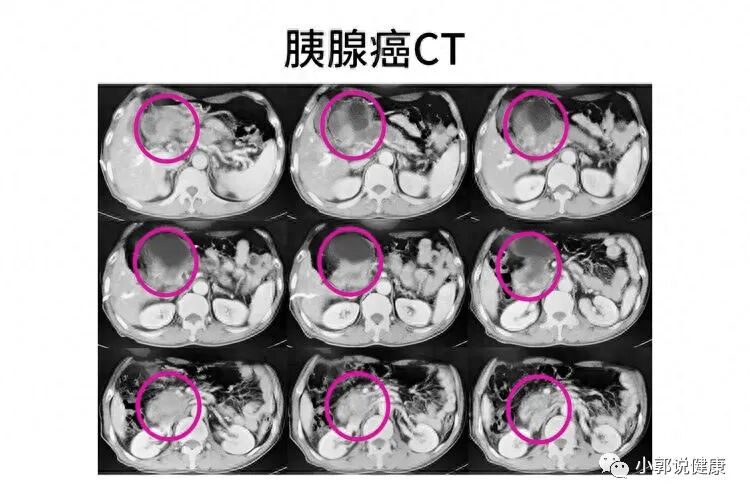

这次他又去医院,并听从医生做了腹部CT,结果一查,就查出胰腺有不明结节样病灶,而最终确诊,就是晚期胰腺癌了。

胰腺被横结肠和胃部遮盖,因而普通检查很难发现胰腺病变,胰腺癌早期诊断率也低。